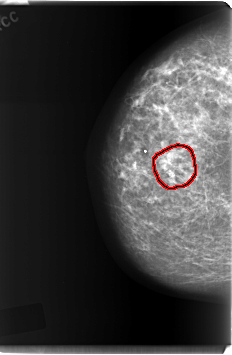

C_0213_1.RIGHT_CC

RIGHT_CC LINES 6032 PIXELS_PER_LINE 3928 BITS_PER_PIXEL 12 RESOLUTION 50 OVERLAY

FILE: C_0213_1.RIGHT_CC.OVERLAY

TOTAL_ABNORMALITIES 1

ABNORMALITY 1

LESION_TYPE CALCIFICATION TYPE PLEOMORPHIC DISTRIBUTION CLUSTERED

ASSESSMENT 5

SUBTLETY 5

PATHOLOGY MALIGNANT

TOTAL_OUTLINES 1

BOUNDARY